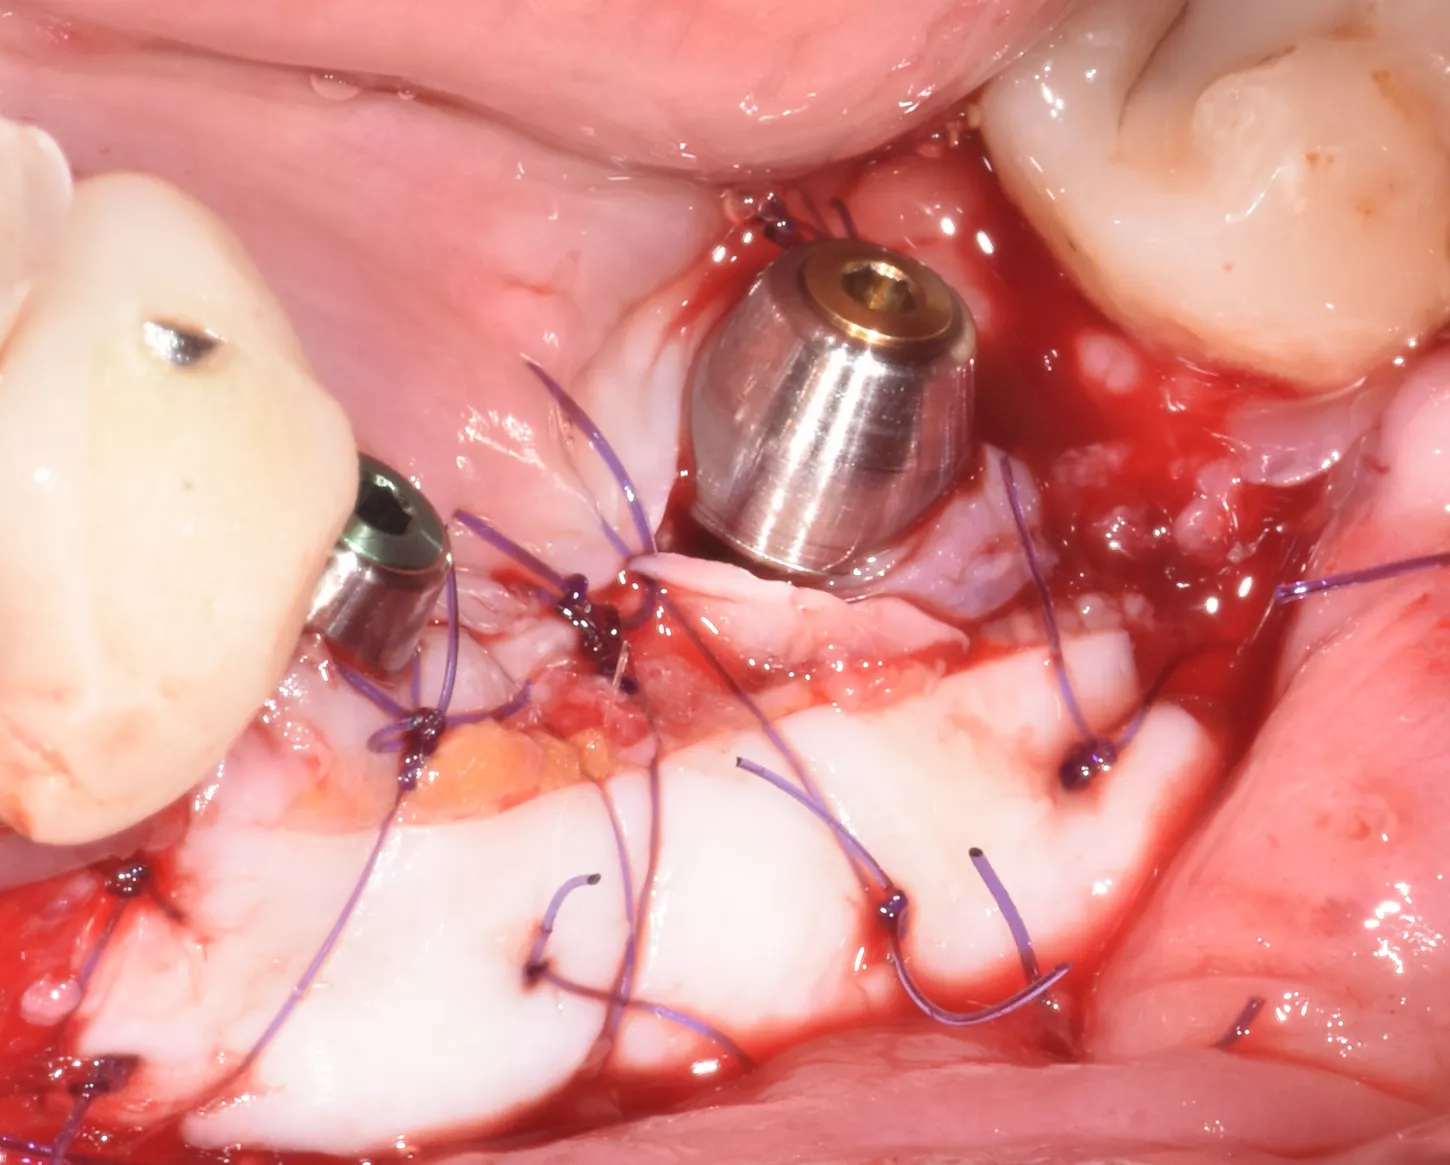

2. Incision and detachment of anatomical structures, highlighting of the inferior dental nerve at the level of its emergence from the mental foramen. 3D bone atrophy is noted. Tissue relaxation is achieved by periosteal incisions in order to release tension and close the site properly.

3 . Split bone block technique using autogenous cortical plates taken from the left ramus according to F. Khoury's protocol.

One buccal plate and one lingual plate are positioned and osteosynthesised with 1 mm Stoma screws.

4. Forming and filling the gap with a mixture of autogenous/xenogeneic bone mixed with PRF (sticky bone).

5. Five months later, the site was reopened and two Axiom X3® Ø4 x 10 mm implants were placed in positions 35 and 36. The implants were positioned infra-crestally using the submerged technique with a torque of 25 Ncm.

6 . Infra crestal position of the implants in the fully regenerated bone.

7. 3 months later: to increase the amount of keratinised tissue, connective epithelial graft with positioning of 2 multi-unit abutments with on the implants was done. ISQ 75.